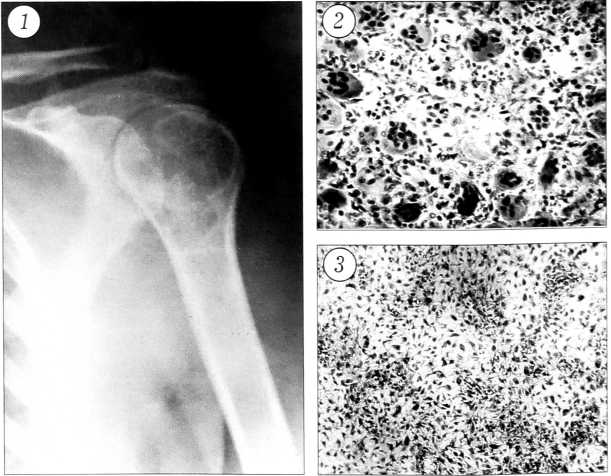

При обследовании обращает на себя внимание атрофия мышц левого плеча. Рентгенологически в проксимальном отделе левой плечевой кости определяется резко выраженное истончение кортикального слоя, головка и шейка замещены патологической тканью литического характера. Заключение: гигантоклеточная опухоль (рис. 1). 15.02.96 произведена трепанобиопсия. Гистологическое заключение: гигантоклеточная опухоль кости.

При цитологическом и гистологическом исследовании в головке обнаружена гигантоклеточная опухоль кости без каких-либо признаков озлокачествления. Определялись гигантские многоядерные остеокластоподобные клетки и «стромальные» одноядерные клетки, имевшие круглую, яйцевидную и веретенообразную форму (рис. 2). В опиле и отдельно присланных кусочках хряща —- хрящевая ткань типа очага хондроматоза, представленного лежащими в лакунарных пространствах мелкими хондроцитами (рис. 3).

Рис. 1. Рентгенограмма больной В.: в проксимальном отделе левой плечевой кости наблюдается резко выраженное истончение кортикального слоя, головка и шейка замещены патологической тканью литического характера.

Рис. 2. Гигантские многоядерные остеокластоподобные и одноядерные клетки гигантоклеточной опухоли кости (окраска гематоксилином и эозином. Ув. 160).

Рис. 3. Относительно часто расположенные мелкие хондроциты очага хондроматоза (окраска гематоксилином и эозином. Ув. 160).